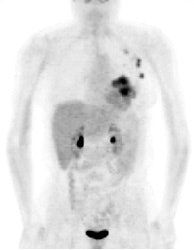

FDG PET exam results in breast cancer patient guide therapy: The patient shown below was a 40 year old female who had undergone lumpectomy and adjuvant chemo/radiation therapy for breast cancer. Ten months later the patient began to experience pain in the right shoulder. A bone scan and CT scan were interpreted as negative. The FDG PET exam revealed numerous foci of tracer accumulation within the right axilla and chest consistent with metastatic disease. As a result of the PET exam findings the patient was treated with another course of chemo/radiation therapy. The exam was performed on a Siemens ECAT EXACT PET scanner; 10 mCi FDG, and 5 bed positions. Case courtesy of Rush-Presbyterian-St. Luke's Medical Center, Chicago, IL and CTI. |

|